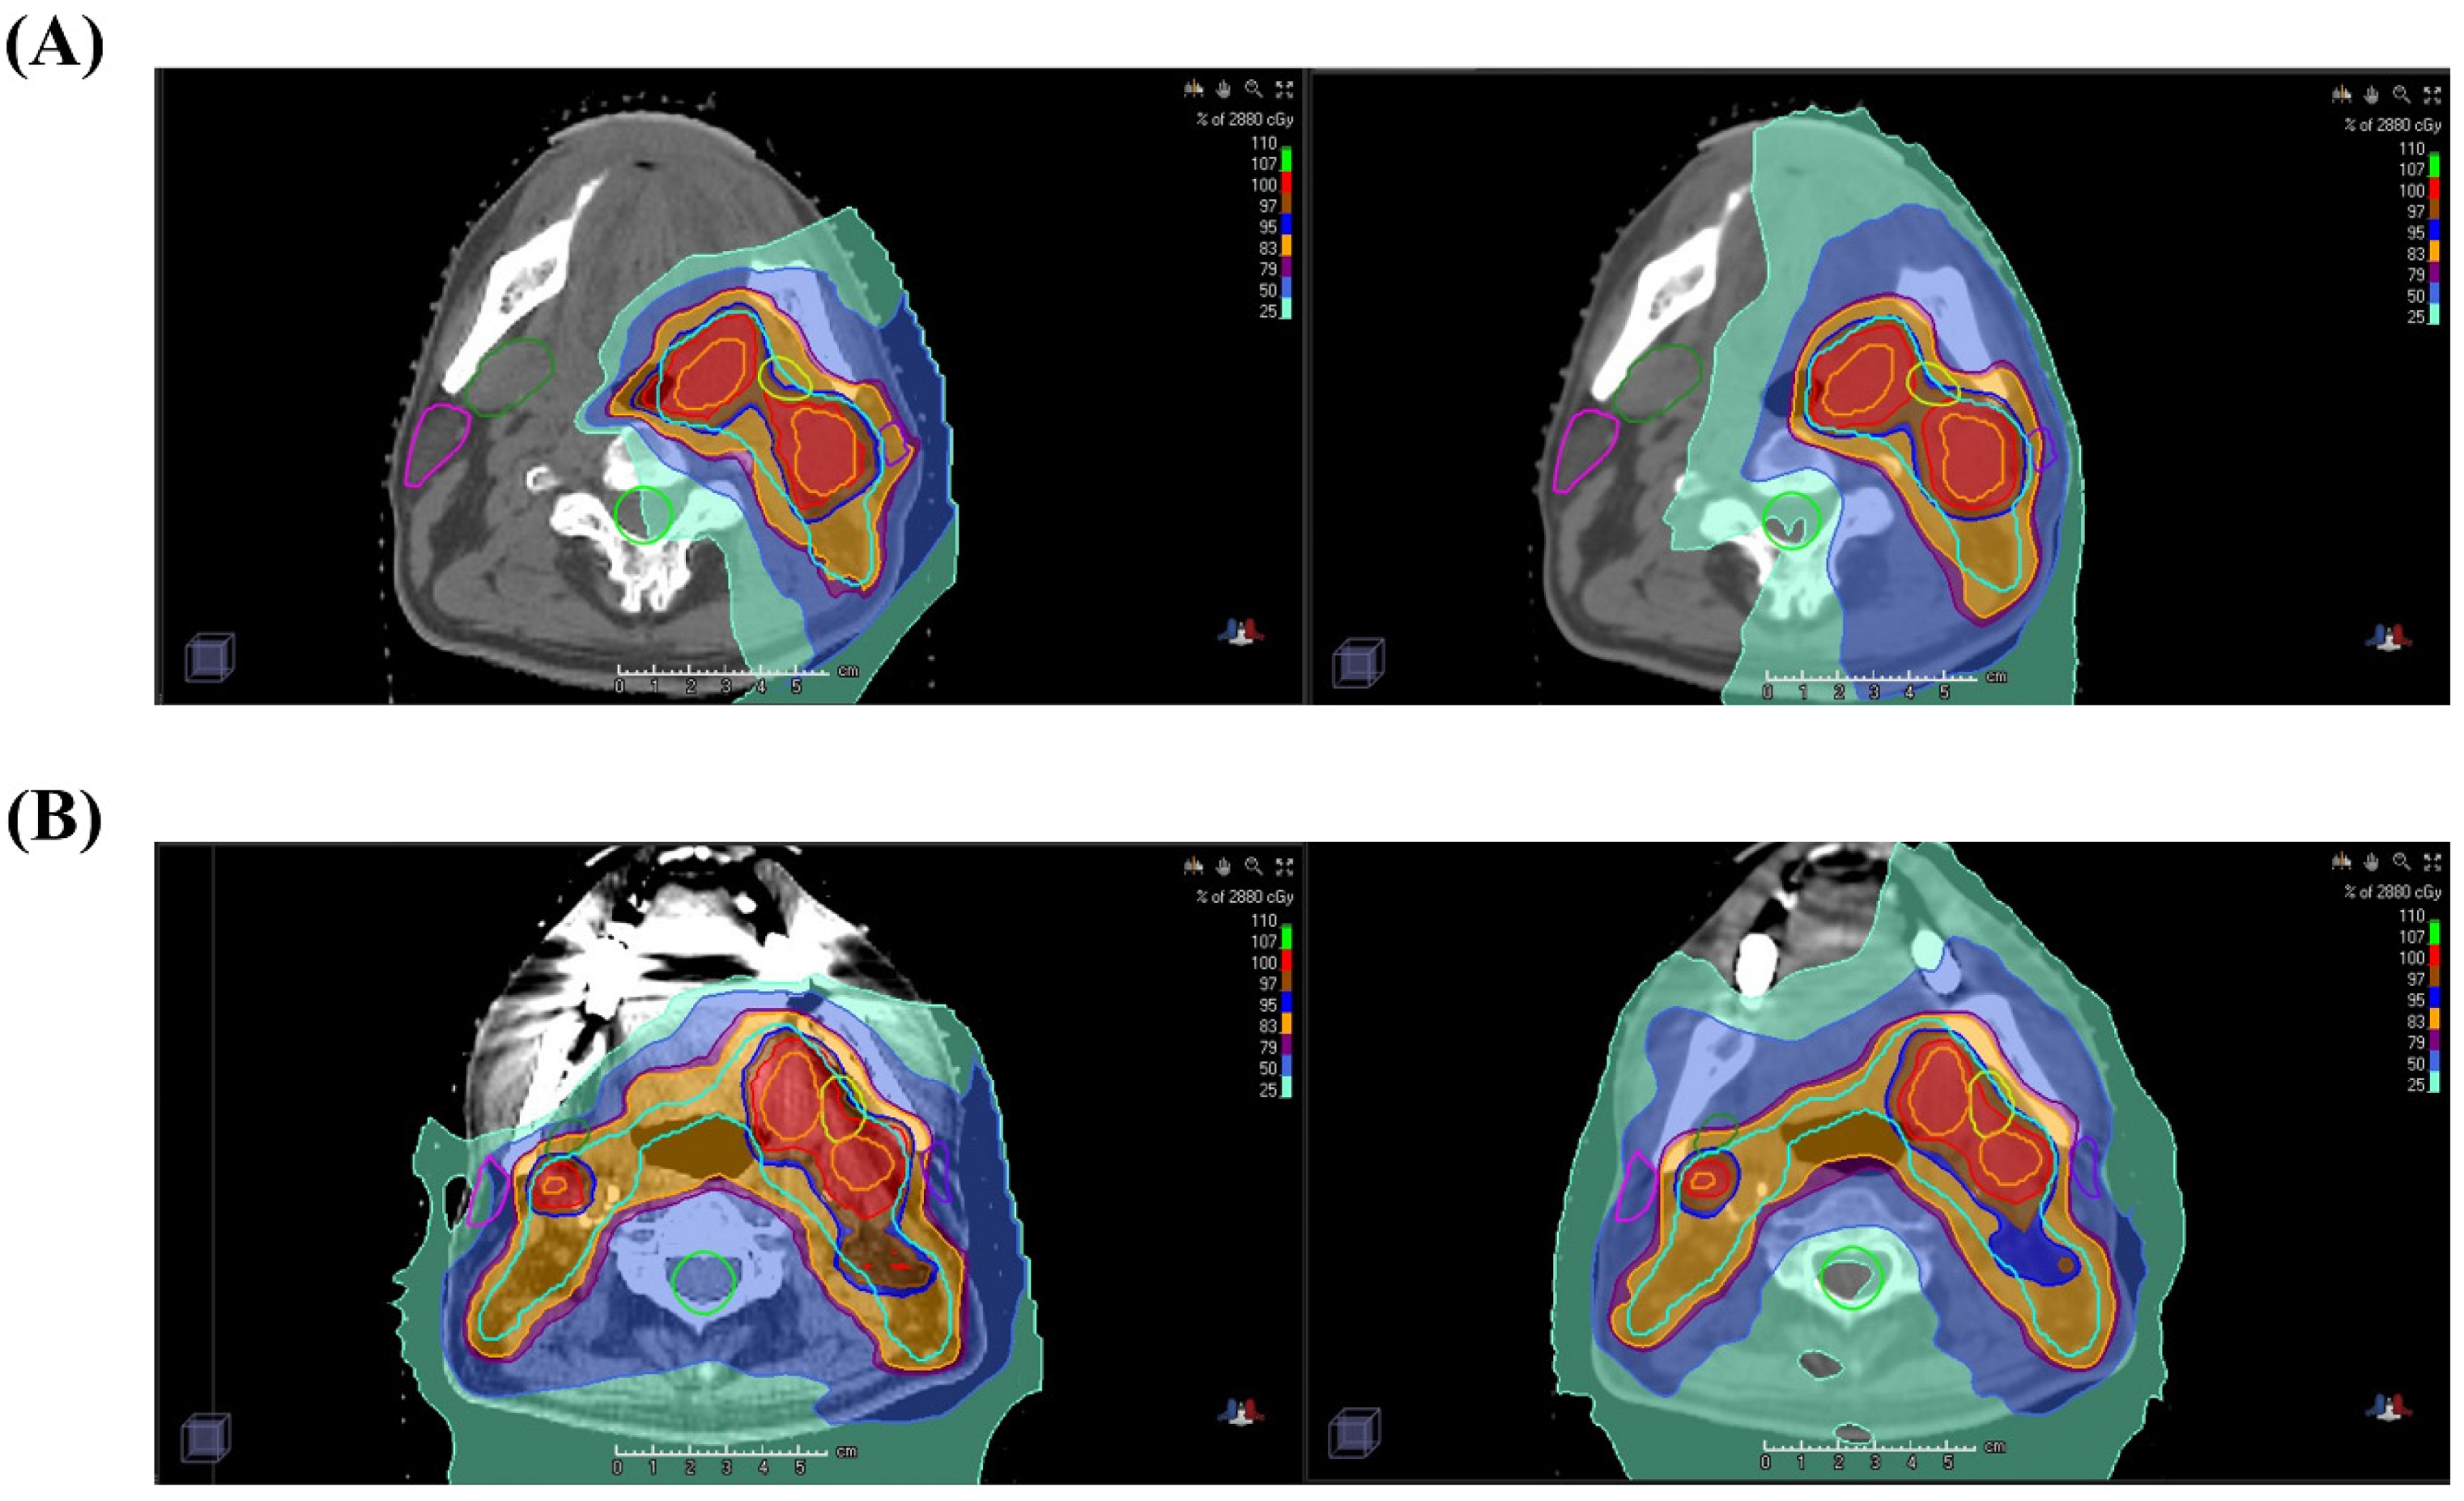

4.2. Treatment Scheme